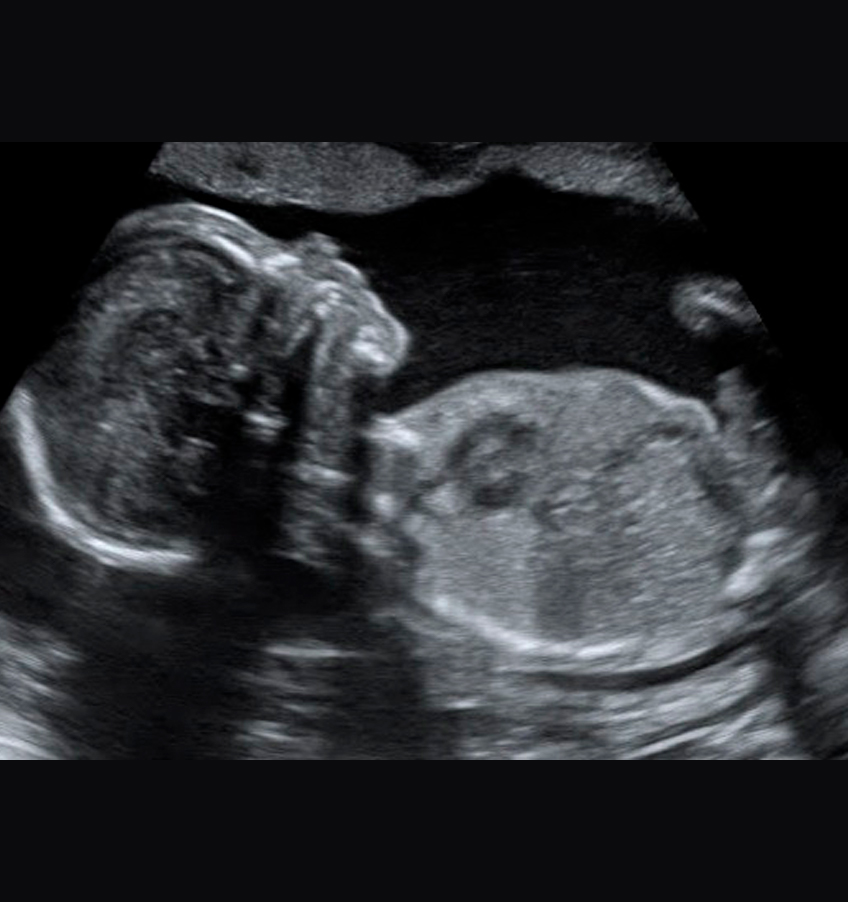

A Ultrassonografia ou ultrassom é um tipo de exame que produz imagens em movimento e em tempo real do feto e de estruturas do corpo. É importante ressaltar que não há radiação e o exame é totalmente seguro durante toda a gestação.

Ultrassons 3D ou 4D

Os ultrassons 3D ou 4D podem ser feitos durante o pré-natal de preferência entre as semanas 26 e 30 e são utilizados para ver detalhes físicos do bebê. O exame em 3D mostra detalhes do corpo do bebê, sendo possível ver o rosto e os órgãos genitais com mais nitidez, enquanto no exame em 4D, além das feições, também é possível visualizar os movimentos do feto na barriga da mãe em tempo real.